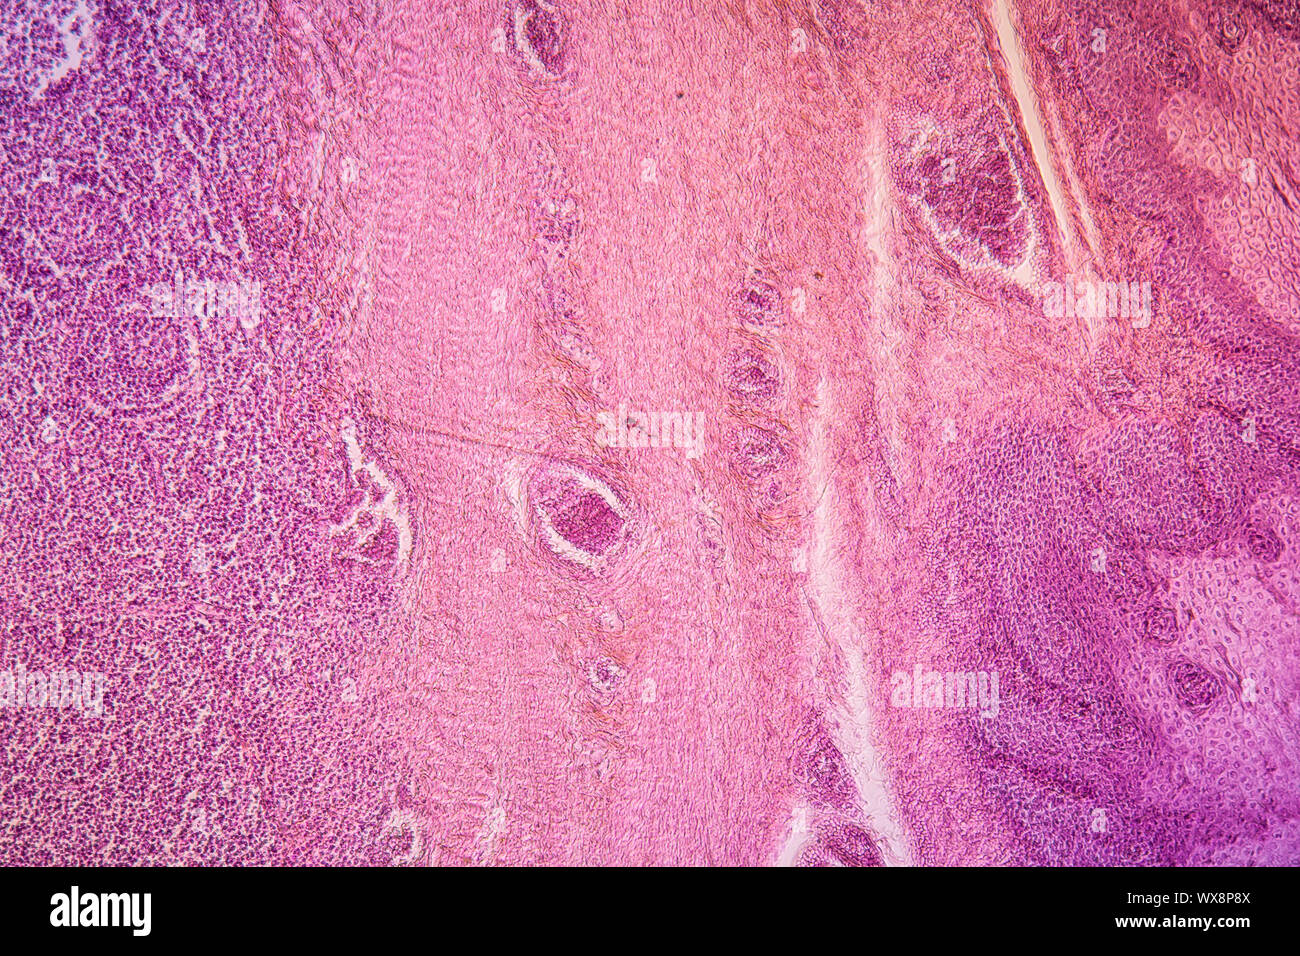

Mandelentzündung krankes Gewebe 100x Stockfotohttps://www.alamy.de/image-license-details/?v=1https://www.alamy.de/mandelentzundung-krankes-gewebe-100x-image274329575.html

Mandelentzündung krankes Gewebe 100x Stockfotohttps://www.alamy.de/image-license-details/?v=1https://www.alamy.de/mandelentzundung-krankes-gewebe-100x-image274329575.htmlRMWX8P4R–Mandelentzündung krankes Gewebe 100x

Mandelentzündung krankes Gewebe 100x Stockfotohttps://www.alamy.de/image-license-details/?v=1https://www.alamy.de/mandelentzundung-krankes-gewebe-100x-image274329690.html

Mandelentzündung krankes Gewebe 100x Stockfotohttps://www.alamy.de/image-license-details/?v=1https://www.alamy.de/mandelentzundung-krankes-gewebe-100x-image274329690.htmlRMWX8P8X–Mandelentzündung krankes Gewebe 100x